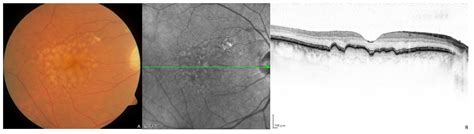

Once you understand the answer to is macular degeneration hereditary, the next logical step is to determine how that information changes your medical care. Modern ophthalmology allows for a more personalized approach based on your risk profile. For instance, patients with high-risk genetic markers may be monitored more frequently with advanced imaging technologies like Optical Coherence Tomography (OCT).